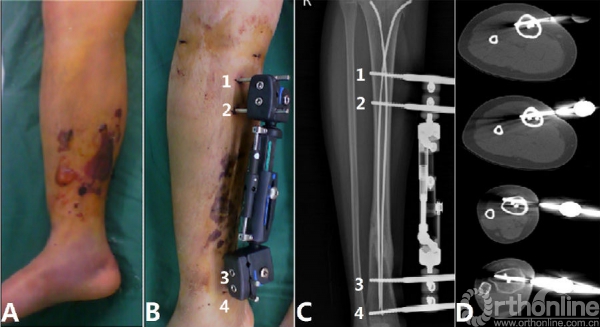

图三